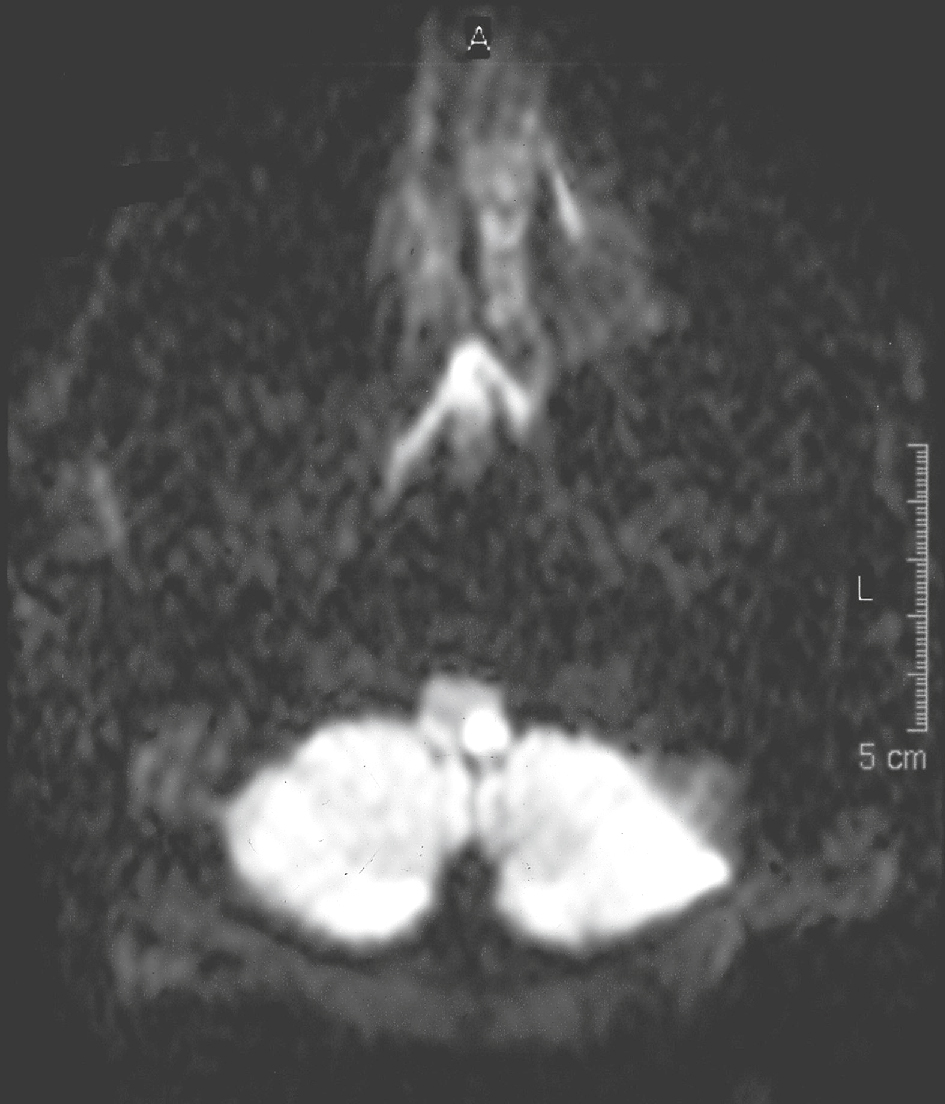

IRM en séquence de diffusion montrant une lésion ischémique récente en hypersignal, de topographie latérobulbaire gauche. Le patient présente un syndrome de Wallenberg.

L'image montre une IRM en séquence de diffusion avec une lésion ischémique récente visible en hypersignal, située dans la région latérobulbaire gauche du cerveau. La séquence de diffusion est une technique d'IRM sensible aux changements dans le mouvement des molécules d'eau, ce qui permet de détecter des lésions ischémiques aiguës. Un hypersignal sur cette séquence indique une restriction de la diffusion des molécules d'eau, typique des infarctus cérébraux récents. La topographie latérobulbaire fait référence à la localisation de la lésion dans la région latérale du bulbe rachidien, une zone du tronc cérébral. Cette localisation est cruciale car le bulbe rachidien joue un rôle important dans le contrôle des fonctions autonomes et des voies nerveuses essentielles. En résumé, l'image d'IRM montre une lésion ischémique récente en hypersignal dans la région latérobulbaire gauche, indiquant un infarctus cérébral aigu avec restriction de la diffusion des molécules d'eau.